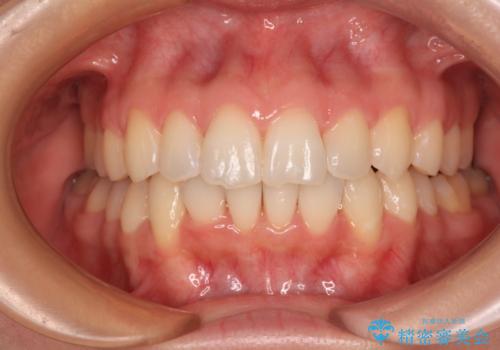

![[ マウスピース矯正 ] 出っ歯に見える前歯を改善したいの症例 治療後](https://seimitsushinbi.jp/wp/wp-content/uploads/2023/10/8a6c9bf89570c0c75da0a5fabd1cd70e-500x350.jpg?v=1697014858)

インビザラインで行う前歯のみの部分矯正